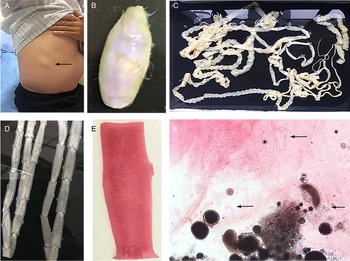

The routine laboratory blood tests, including eosinophil and lymphocyte count, were completely normal apart from the elevated inflammation markers (C-reactive protein and neutrophil count). Schistosomes, Clonorchis sinensis, Echinococcus granulosus and Toxoplasma gondii antibodies were negative in his serum, as were Cryptococcus capsular antigen and next-generation sequencing results from cerebrospinal fluid. Multiple intracranial nodules affecting the supratentorial and infratentorial cerebral parenchyma were shown in detail on CT and MRI of the head, indicating possible intracranial parasitic infection (Fig. 1). Ultrasound scan confirmed the presence of 2 palpable and soft masses located in muscles, which were approximately 19 × 8 × 15 mm3 under the right chest wall and 26 × 10 × 19 mm3 under the right midaxillary line (Fig. 2). A subsequent biopsy of the mass (Fig. 3) showed larval-like tissue, peripheral fibrous tissue hyperplasia, lymphocytic infiltration and hyaline degeneration. The patient was probably diagnosed with taeniasis and cysticercosis and treated with oral albendazole (400 mg, twice daily) over 2 weeks. Hydrocortisone 50 mg was provided 2 days after the first albendazole treatment to counteract any potential negative effects on the central nervous system. After only 2 days of this antiparasitic treatment, the adult tapeworm was eliminated through the patient's feces (Fig. 3). When compared with the first MRI (half a month before antiparasitic treatment), the second MRI (half a month after antiparasitic treatment) demonstrated a slightly smaller focus (Fig. 1). The headache and vomiting resolved, and the patient remained symptom free over a 3-month follow-up period.

Fig. 3. Tapeworm materials from the patient: (A) subcutaneous mass; (B) cyst; (C) adult tapeworm; (D) unstained proglottids; (E) a stained proglottid and (F) cystic lesion with hydrochloric acid-carmine staining showing presumed deciduous hooks (black arrows).

Morphological observation

The adult tapeworm was milky white, flat and long like a belt, thin and translucent, and the main segments are shown in Fig. 3. The uterine branches in the gravid proglottids were regular, and each side had approximately 15–30 branches (Fig. 3). The slide of the cyst showed no obvious typical features; however, some presumed deciduous hooks were found in the same slide, leading to indistinguishable morphology (Fig. 3).

Three common Taenia species can be differentiated by examination of their morphological characteristics, such as the scolex, mature and gravid proglottids in the adult stage, and the scolex in the larval stage (Eom et al., Reference Eom, Rim and Jeon2020). However, the differential diagnosis between them is challenging when their morphology is not so typically visible. As far as morphological characteristics were concerned, the gravid proglottids (Fig. 3) from this patient were the same as T. saginata or T. asiatica, not T. solium, while the morphological evaluation of cysticercosis, that showed the presence of detached hooks (Fig. 3), referred to T. asiatica and T. solium rather than T. saginata. However, the traditional morphological taxonomy has some inherent limitations leading to possible false-species identification and can neglect cryptic or pseudocryptic species. That is the reason why integrated taxonomy approaches, wherein molecular studies combine detailed morphological information, are important in helping characterize pairing at the individual level resulting in the perfect characterization of cryptic biodiversity (Hebert et al., Reference Hebert, Cywinska, Ball and deWaard2003; Laakmann et al., Reference Laakmann, Blanco-Bercial and Cornils2020).